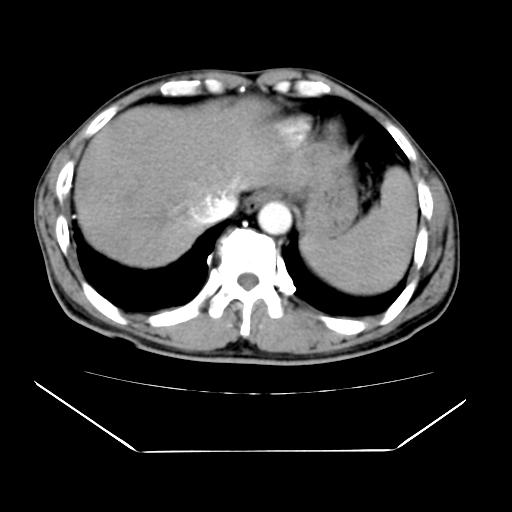

男性,55岁,外院体检afp明显升高,但b超未发现异常,否认乙肝病史。来我院ct增强。有延时扫描。

延时扫描完全充填,血管瘤

肝脏右叶动脉期可见低密度影,至延迟期被充填,考虑血管瘤可能性大。

不排除肝右叶肝癌可能。

如果这个是癌灶的话则下腔静脉有瘤栓可能

肝6段血管瘤

血管瘤可能性大。

考虑肝右静脉影。